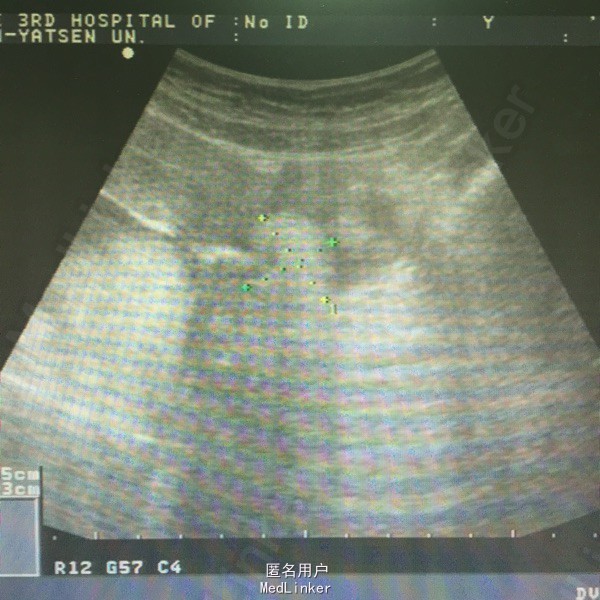

患者女性,20岁,因右下腹痛1天急诊入院。未婚无性生活史。

肛查:双侧附件区个扪及一肿物,右侧6*6cm,无压痛、反跳痛,左侧3*3cm,有压痛,无反跳痛。阑尾彩超未见明确显示。血常规白细胞及中性粒细胞百分率升高。彩超子宫双附件:双侧附件区混合性肿块,右侧60*54mm,左侧38*21mm,呈面团征,后方回声增强,考虑畸胎瘤可能性大。

诊断:双侧卵巢畸胎瘤,左侧卵巢蒂扭转。行腹腔镜检查,术中见右侧输卵管扭转180°,卵巢表面血运良好,予行双侧卵巢囊肿剔除,标本中查见毛发及油脂。术后病理:双侧卵巢成熟性畸胎瘤。